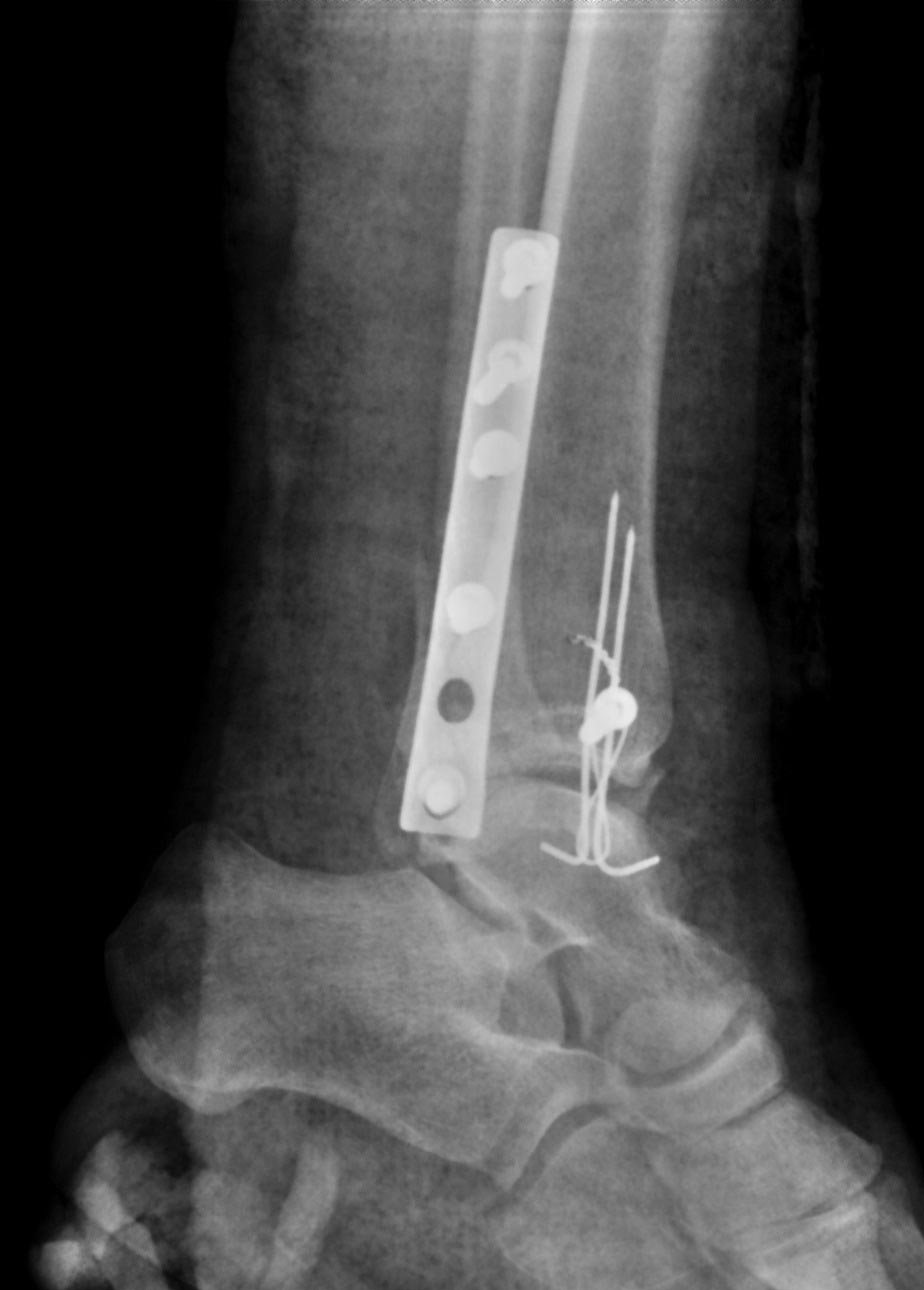

Здравствуйте. Операция 2 дня назад по дежурству, объем движений в голеностопном суставе полный.

Пациенту 35 лет. Ограничиться заменой длинных винтов либо делать реостеосинтез малоберцовой кости?